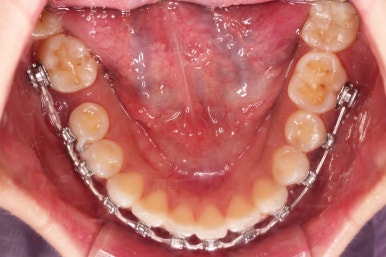

3. 치료경과

장치를 부착했고요.

이번에 환자분이 선택한 장치는 윗니는 자가결찰 세라믹, 아랫니는 자가결찰 메탈이었습니다.

이렇게 혼용해서 사용해도 되는 조합들이 있고요.

이번 환자분은 웃을 때 이가 많이 보이는 타입이 아니셔서 아랫니는 좀 더 튼튼하고 저렴하기까지한 메탈장치를 선택하셨죠.

적절한 시점에 발치를 합니다.

발치는 가장 약한 치아 위주로 하게 되고요.

윗니는 이 뽑은 자리를 줄여나가고요.

아랫니는 어금니와 사랑니를 앞으로 당겨옵니다.

물론 다른 치아에 변화를 주지 않기 위해서 미니스크류를 이용합니다.